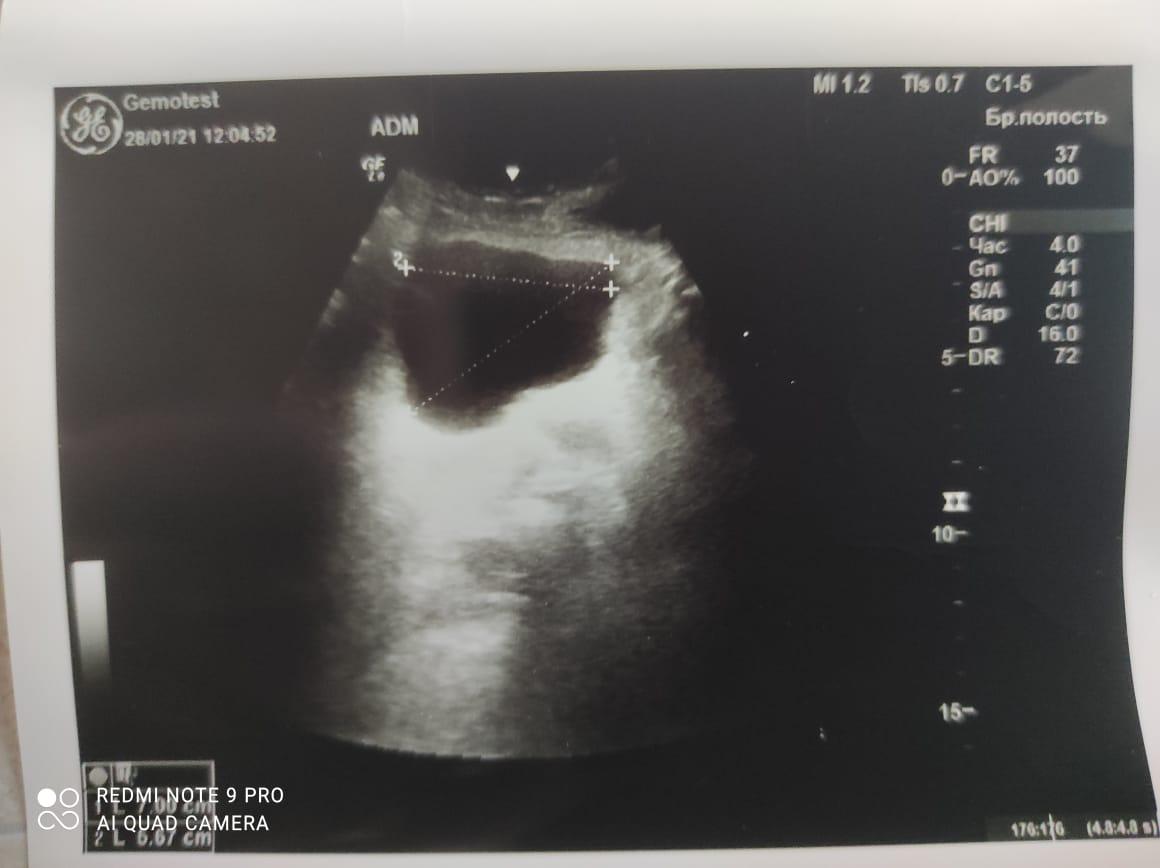

Здравствуйте! При наличии коралловидного камня правой почки(заключение УЗИ), можно предположить причиной боли нарушение уродинамики верхних мочевых путей), что, однако, не подтверждается результатами УЗИ почек( ЧЛС не расширена). Другая, наиболее вероятная возможная причина "боли в боку" - может быть патология опорнодвигательного аппарата. Необходимо проконсультироваться с неврологом и урологом очно, и согласовать возможность применения противовоспалительных, обезболивающих и спазмолитических препаратов - как первый шаг. В дальнейшем необходимо планировать возможное дальнейшее обследование и лечение. Удачи!